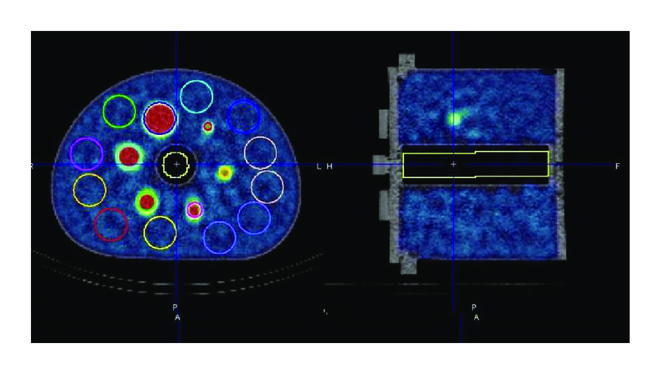

We started our investigation by assessing quantitative accuracy in terms of activity concentration recovery in a simple geometric configuration consisting of a uniform background (cylindrical homogenous phantom). The cylindrical phantom was 18 cm long and 20 cm in diameter for an inner volume of 5683 mL. The SPECT reconstruction for the cylindrical phantom employed 24 iterations, 4 subsets, and a Gaussian smoothing with a full width at half maximum (FWHM) of 7.5 mm. This represents the standard quantitative reconstruction algorithm in our clinical setup. The accuracy was evaluated by a calibration factor (Bg. cal) which was the ratio between the activity concentration measured in the reconstructed SPECT phantom background () and the expected activity concentration () known from the phantom preparation: was evaluated as the average on 5 circular region of interests of 16 cm diameter centered on the cylinder axis placed at different axial locations (Figure 1(a)). The image noise was evaluated by the coefficient of variation (COV), which is the ratio between the standard deviation and the average signal measured from the phantom background:To test the influence of the count statistics on quantitative accuracy, we performed successive SPECT acquisitions at different time points. The total activity in the phantom and thus the background activity concentration decreased as a function of time elapsed between the phantom preparation and the actual acquisition time. The nominal activity concentration in the phantom background at the time of the acquisition, the calibration factor, and the coefficient of variation are reported in Table 1.

Six spherical inserts 10, 13, 17, 22, 28, and 37 mm in diameter were filled with an activity concentration () 8.5 times higher than the activity concentration present in the phantom background (as reported in Table 2). A lung insert was also available for this phantom and used to estimate a relative lung error () (see Figure 1(b)).

Lastly, we assessed quantitative accuracy using an anthropomorphic abdominal phantom (commercial Kyoto Liver/Kidney phantom, Nuclemed, Roeselare, Belgium) that includes a liver insert (volume = 1.8 L) with 3 hot-spheres (20–30–40 mm diameter, 5.2 : 1 hot-sphere to liver activity concentration ratio) and a high-density element such as a lumbar spine insert (Figure 1(c)). We assessed the hot contrast for the three spherical inserts.